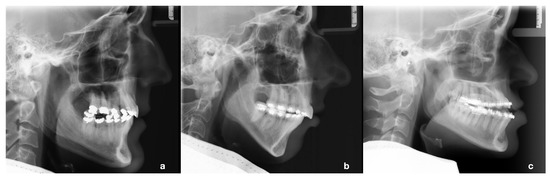

- Stamm, T.; Andriyuk, E.; Kleinheinz, J.; Jung, S.; Dirksen, D.; Middelberg, C. In Vivo Accuracy of a New Digital Planning System in Terms of Jaw Relation, Extent of Surgical Movements and the Hierarchy of Stability in Orthognathic Surgery. J. Pers. Med. 2022, 12, 843. [Google Scholar] [CrossRef] [PubMed]

- Stamm, T.; Böttcher, D.; Kleinheinz, J. The University Münster Model Surgery System for Orthognathic Surgery—The Digital Update. Head Face Med. 2021, 17, 31. [Google Scholar] [CrossRef]

- Ehmer, U.; Joos, U.; Flieger, S.; Wiechmann, D. The University Münster Model Surgery System for Orthognathic Surgery. Part I—The Idea Behind. Head Face Med. 2012, 8, 14. [Google Scholar] [CrossRef] [PubMed]

- Ehmer, U.; Joos, U.; Ziebura, T.; Flieger, S.; Wiechmann, D. The University Münster Model Surgery System for Orthognathic Surgery. Part II—KD-MMS. Head Face Med. 2013, 9, 2. [Google Scholar] [CrossRef] [PubMed]